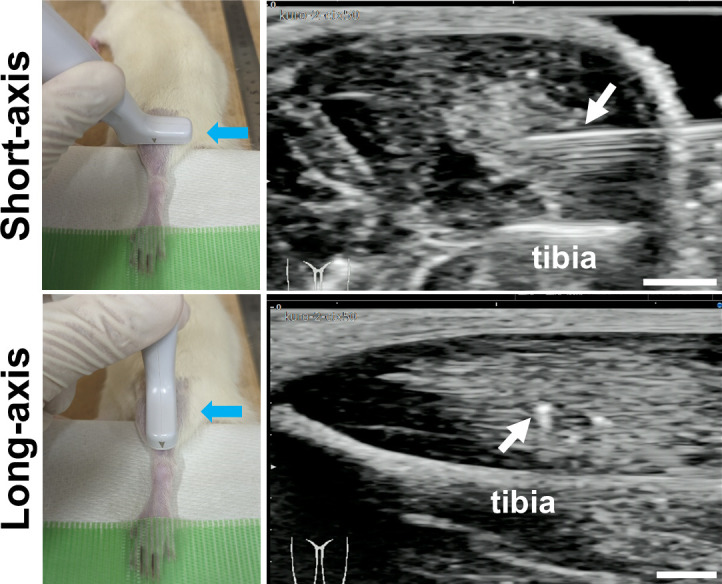

Methods: A cardiotoxin (CTX)-induced muscle injury model was used. Briefly, CTX was injected into tibialis anterior muscle in rats under ultrasound observation. First, the diagnostic accuracy of abnormal muscle lesions on ultrasound was examined by comparing ultrasound findings and histology. Next, Fast Green solution and green fluorescent protein (GFP)-labelled cells were simultaneously injected into the abnormal muscle lesions under ultrasound guidance, and their distribution was evaluated.

Results: Evaluation of short-axis ultrasound images and cross-sectional histological staining showed a strong correlation (r = 0.927; p < 0.001) between the maximum muscle damage area in ultrasound and haematoxylin and eosin (H&E) staining evaluations. Histological analysis showed that ultrasound-guided injection could successfully deliver Fast Green solution around the myofibres at the site of injury. In contrast, the distribution of injected cells was very localized compared to the area stained with Fast Green.